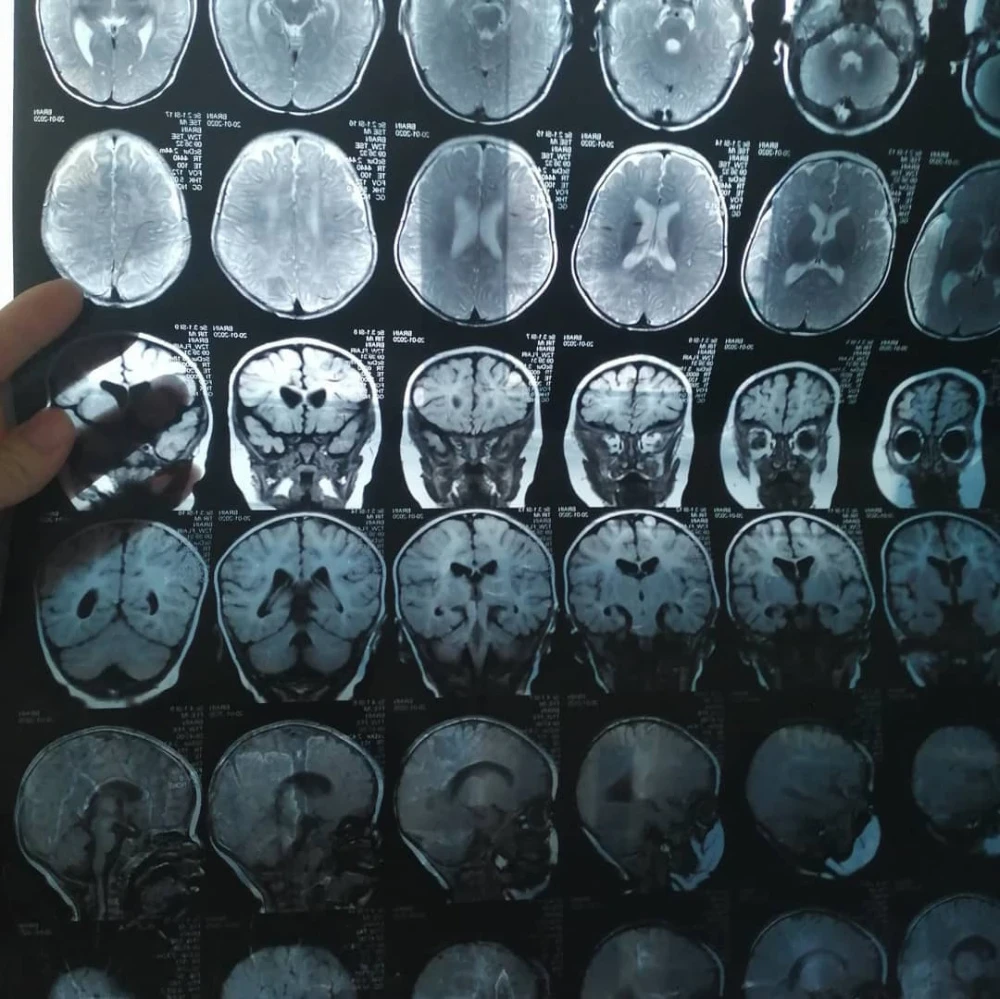

Aykol has a number of complex diagnoses and needs help.

Aykol has undergone two surgeries in Bishkek to correct the deformity of her ankle joint, but unfortunately, they did not yield the desired results.